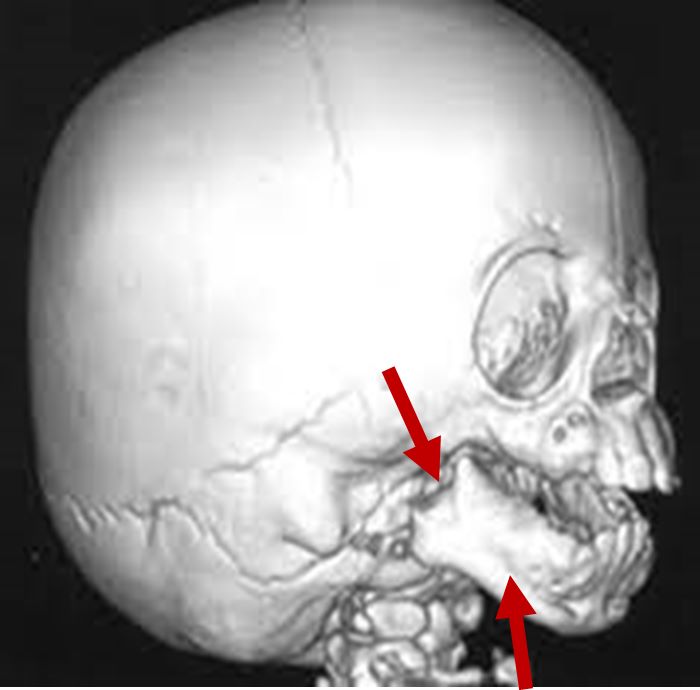

Zygomatic hypoplasia

3D CT scan showing missing zygomatic arch

Radiographical features source 4